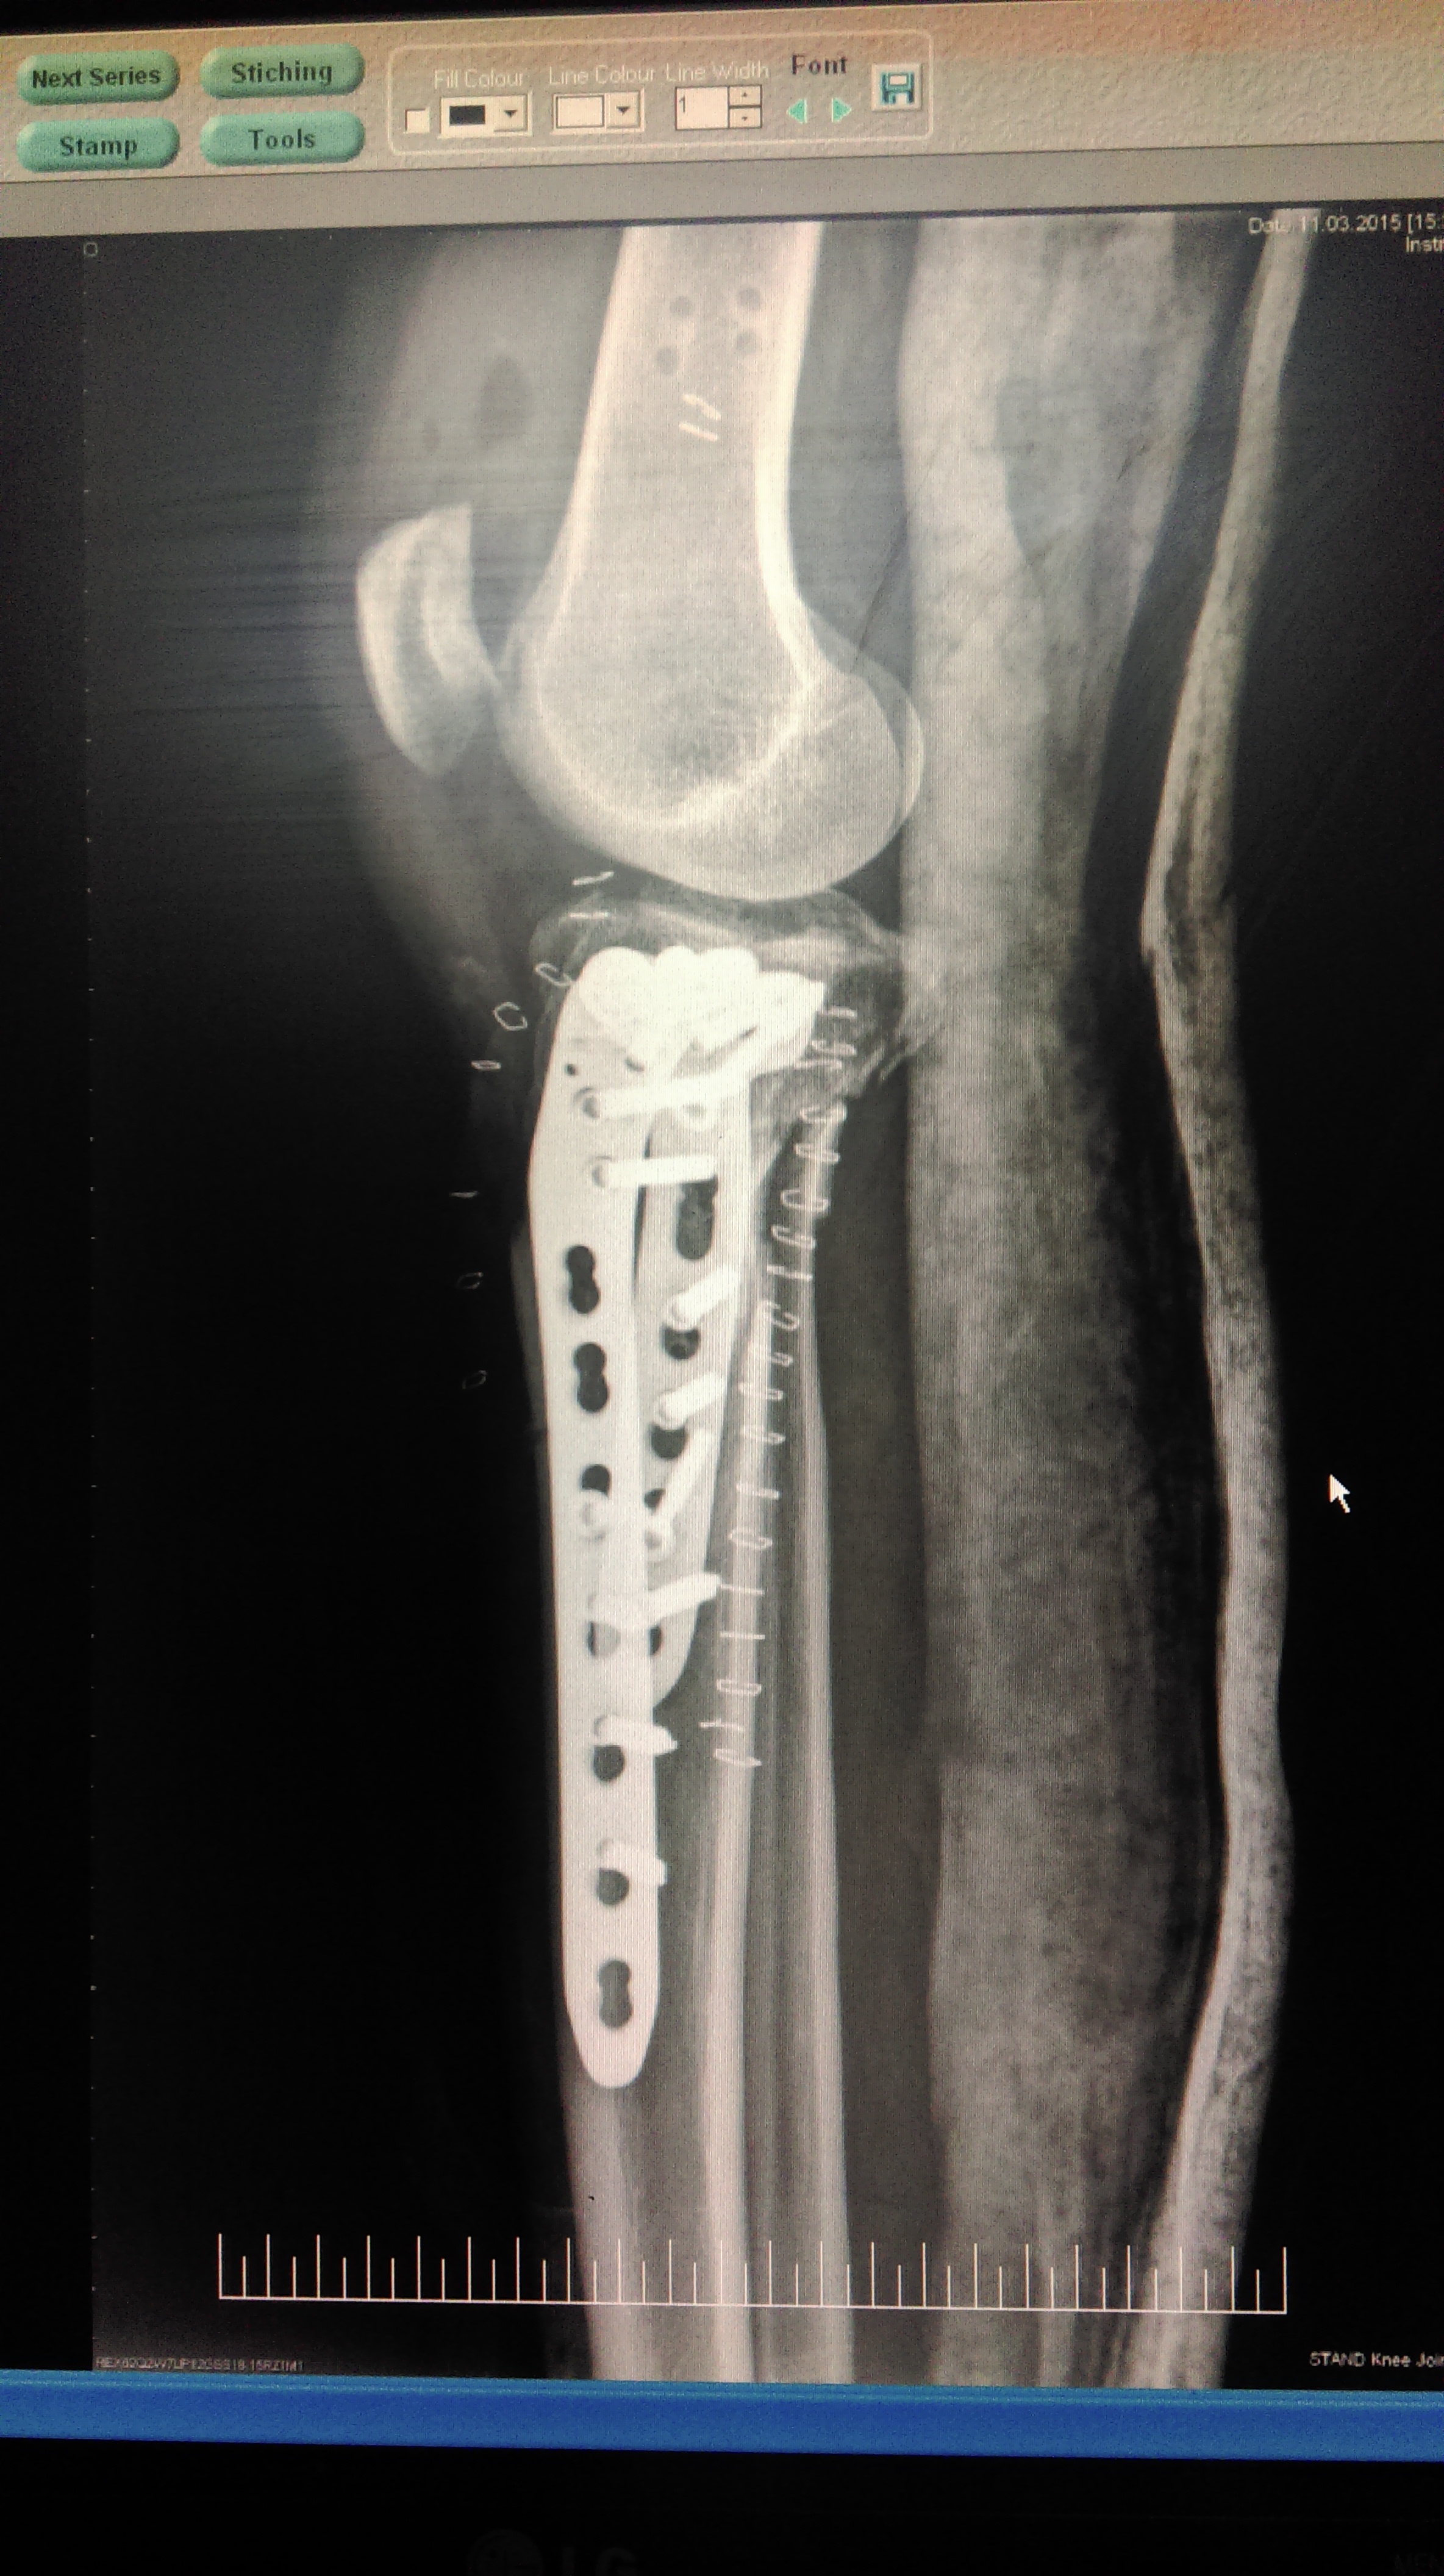

Total Knee replacement is a surgical procedure in which parts of an arthritic or damaged joint are removed and replaced with a metal, plastic, or ceramic device called a prosthesis. The prosthesis is designed to replicate the movement of a normal, healthy joint.

During the surgery, the damaged cartilage and bone is removed from your joint and replaced with prosthetic components made of metal, plastic, or ceramic. The prosthesis mimics the shape and movement of a natural joint.

Restoration of the normal motion of the knee joint and functioning without replacement is achieved by different methods of joint care and it is known as “knee joint preservation”. The approach of preserving the knee joint helps orthopedic surgeons to treat knee joint problems while retaining the natural structure of the affected joints. Techniques of knee joint preservation are used primarily in persons having defects in the articular cartilage of the knee.